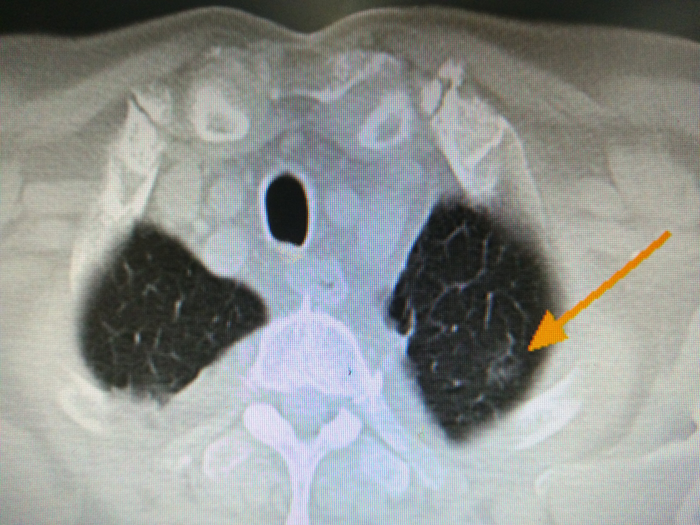

左上肺磨玻璃灶,约1.5cm。

活检加单针射频消融,一共30min,非常顺利,没有气胸,没有咯血。做完第二天,周老师就出院了。病理提示前列腺癌肺转移可能。6个月后,他第二次来复查。CT上磨玻璃影已经消失了,只剩下一个条索影。周老师很激动,不住的夸他自己慧眼识英雄,在众多治疗中选对了射频,选对了医生?